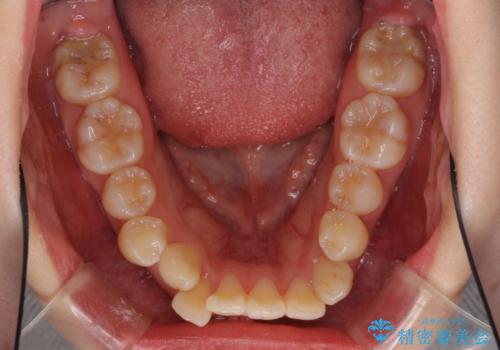

- 口元の突出感を気にして来院された患者様です。

診断の結果、上顎左右第一小臼歯4本抜歯により、叢生を解消するとともに口元を引っ込めていくことが望ましいと判断しました。

抜歯矯正による口元の改善にはワイヤー矯正が望ましいのですが、ダンサーとしての仕事を行っているため、インビザラインにて治療を行うこととしました。